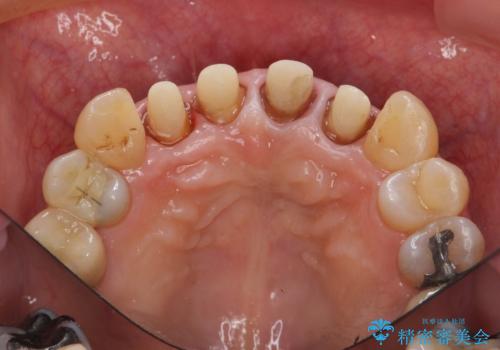

クラウン治療は経年的に歯ぐきの位置が変わり汚れが溜まってしまったり、見た目が悪くなるなどの問題が出てくることがあります。

現在の歯ぐきの位置できっちりと仕上げることで見た目の改善が達成されました。